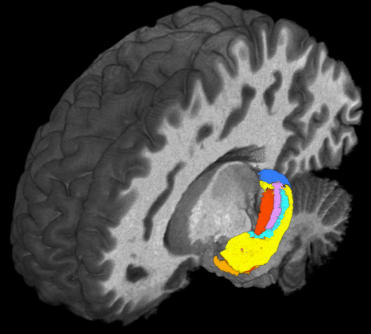

Using ultra-high field magnetic resonance imaging (MRI) to map the brains of people with Down syndrome (DS), researchers from Case Western Reserve University, Cleveland Clinic, University Hospitals and other institutions detected subtle differences in the structure and function of the hippocampus—a region of the brain tied to memory and learning.

Such detailed mapping, made possible by the high-powered MRI, is significant because it allowed the research team to better understand how each subregion of the hippocampus in people with DS is functionally connected to other parts of the brain.

Taking advantage of the increased resolution afforded by high-powered MRI, the researchers performed the first in-vivo comparison of volumes of different anatomical segments of the hippocampus between people with DS and “control” individuals of the same age and sex without DS.

“The gains in sensitivity and image resolution achievable with ultra-high field MRI provide levels of detail and accuracy that have not previously been attainable in studies of live, non-sedated individuals with Down syndrome,” said Katherine Koenig, Ph.D., an assistant professor of radiology at the Cleveland Clinic Lerner College of Medicine of Case Western Reserve University and the study’s first author.